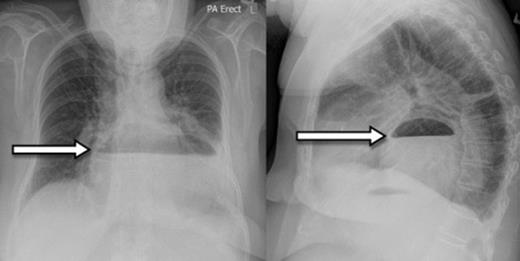

A 73-year-old Caucasian woman presented to the emergency department with 2-day history of vomiting and vague abdominal pain. Her background history included asymptomatic hiatus hernia, morbid obesity (BMI of 35.7), polymyalgia rheumatica, previous laparoscopic cholecystectomy, hypercholesterolaemia and hypertension. Regular medications included prednisone, amlodipine and cilazapril. On presentation she was tachycardic at 110 beats/min with otherwise normal vital signs. Her abdomen was generally tender but without any localised peritonism. Initial laboratory investigations on admission showed a leukocytosis (WCC of 13.8 x 109/L). Routine X-ray (figure 1) and subsequent (CT) scan (figure 2) both revealed a large strangulated paraoesophageal hernia. Radiographic changes (figure 3) were seen with gas within stomach wall, suggestive of gastric necrosis.

CT showing gas within stomach wall (arrow) suggestive of gastric necrosis